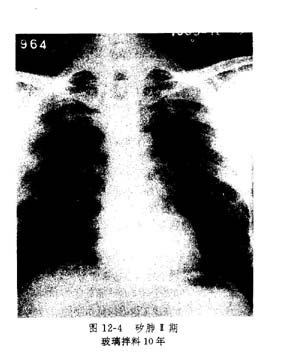

3.二期尘肺(代号Ⅱ),(参见图124)

(1)Ⅱ有密集度2级的类圆形或不规则形小阴影,分布范围超过四个肺区;或有密集度3级的小阴影,分布范围达到四个肺区。

(2)Ⅱ+有密集度为3级的小阴影,其分布范围超过四个肺区;或有大阴影尚不够为"Ⅲ"者。